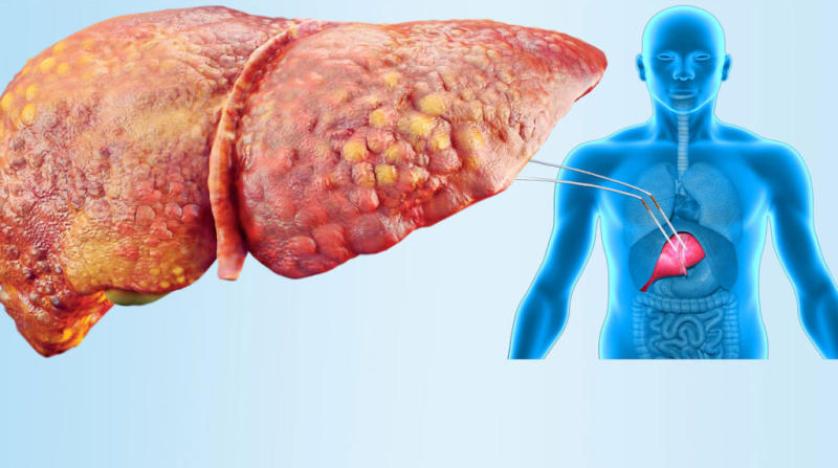

ما هو مرض الكبد الدهني؟

الكبد هو أكبر عضو داخلي في الجسم، ويحدث مرض الكبد الدهني عندما يكون هناك الكثير من الدهون المتراكمة في الكبد لأسباب مختلفة.